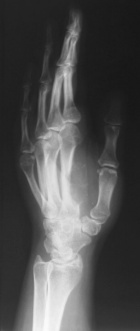

M.S. - 31 year old female complains of pain in her right first web space and index finger; pain began six months ago, but x-rays were not taken until recently since the patient was pregnant